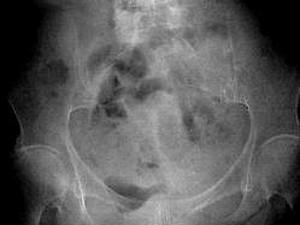

问题 女,69岁,阵发性腹痛伴恶心呕吐7h,10年前因右侧腹股沟斜疝行手术治疗,因急性肠梗阻行CT扫描如图,最可能的诊断是 ( )

选项 A、半月线疝 B、闭孔疝 C、股疝 D、腹外斜疝 E、急性肠梗阻

答案 B